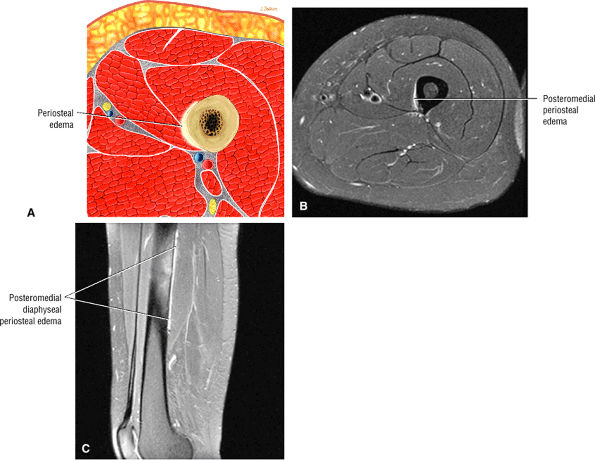

Chondral fissures or defects, joint space narrowing, and femoral head edema, seen in the advanced stages of FAI

-

Thickening of the iliofemoral ligament and synovitis adjacent to the capsule and proximal femur